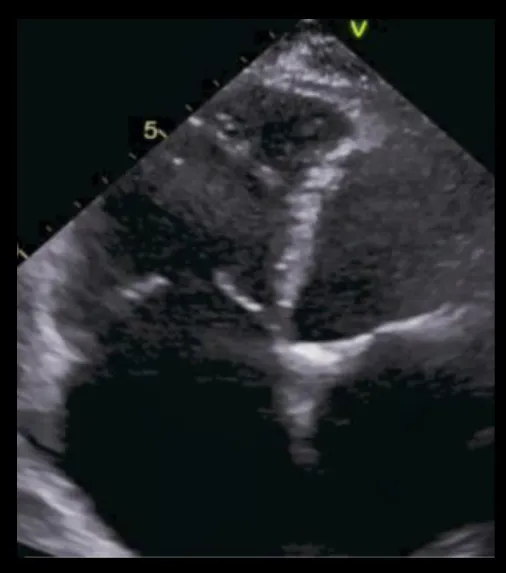

Figure 1

Pathophysiologic Subdivision of Tricuspid Regurgitation. Primary tricuspid regurgitation is caused by abnormalities/damage on the tricuspid valve apparatus (A) (e.g., prolapse of the leaflet or endocarditis). Left heart related tricuspid regurgitation and precapillary pulmonary tricuspid regurgitation (B) are caused by dilation of the right ventricle, papillary muscle displacement and tethering of the tricuspid valve leaflets with malcoaptation. In isolated tricuspid regurgitation (C) the tricuspid annulus is pronouncedly dilated due to dilation of the right atrium in the presence of atrial fibrillation or diastolic dysfunction.

Akin to mitral regurgitation, TR may be of primary (degenerative) or secondary (functional) origin. Primary tricuspid regurgitation (PTR) occurs less frequently (8–10% of all-cause TR) (2). In PTR abnormalities of the tricuspid valve apparatus may be of congenital or acquired origin. Apical displacement of the tricuspid leaflets that arise directly from the right ventricle without being linked to chordae is the most common congenital cause of primary TR (Ebstein's disease) (3). Acquired primary tricuspid regurgitation is mostly caused by leaflet perforation and entrapment following device placement (4). Considering a continuously aging population with an increased need for cardiac pacemaker-implantation, the prevalence of pacemaker/lead-induced TR may increase and should be considered in future device selection as novel techniques such as his bundle pacing and leadless pacemakers are quickly becoming available (5). Another important entity of PTR is endocarditis (Figure 1A), which makes up 17% of all endocarditis cases, predominantly occurs in males and is very often a consequence of intravenous drug abuse or is also related to implantable devices. It affects the anterior leaflet and manifests with large vegetations in the majority of cases (6, 7). Rarer causes of PTR are chordae rupture following right-ventricular biopsies often seen after cardiac transplantation or hepatically metastased neuro-endocrine tumors (Hedinger syndrome), which involve the heart and particularly the tricuspid valve in 60% resulting in fibrotic stiffening of the leaflets (8).